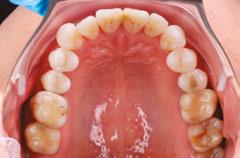

Interproximal recontouring is a crucial component of orthodontic treatment that involves the careful reshaping of tooth surfaces where they touch. This procedure is essential for creating space for teeth movement, improving alignment, and enhancing overall smile esthetics.

Conclusion

Interproximal recontouring is a valuable adjunct to orthodontic treatment that significantly contributes to achieving optimal esthetic outcomes. By carefully selecting and applying appropriate techniques, clinicians can effectively address crowding, diastema, and other dental irregularities, resulting in improved tooth alignment, spacing, and overall facial harmony.